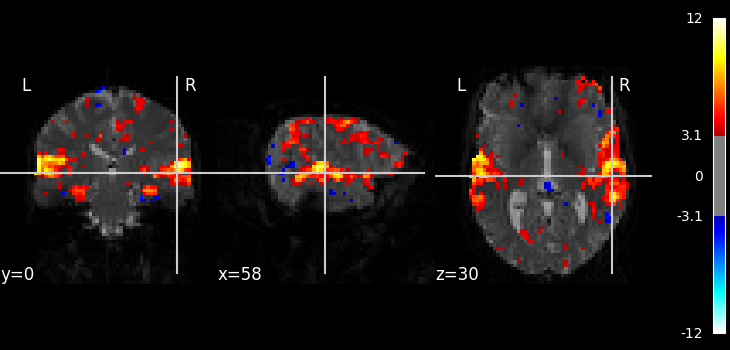

Calculate and plot contrast¶

from nilearn import plotting

z_map = fmri_glm.compute_contrast("active - rest")

plotting.plot_stat_map(z_map, bg_img=mean_img, threshold=3.1)